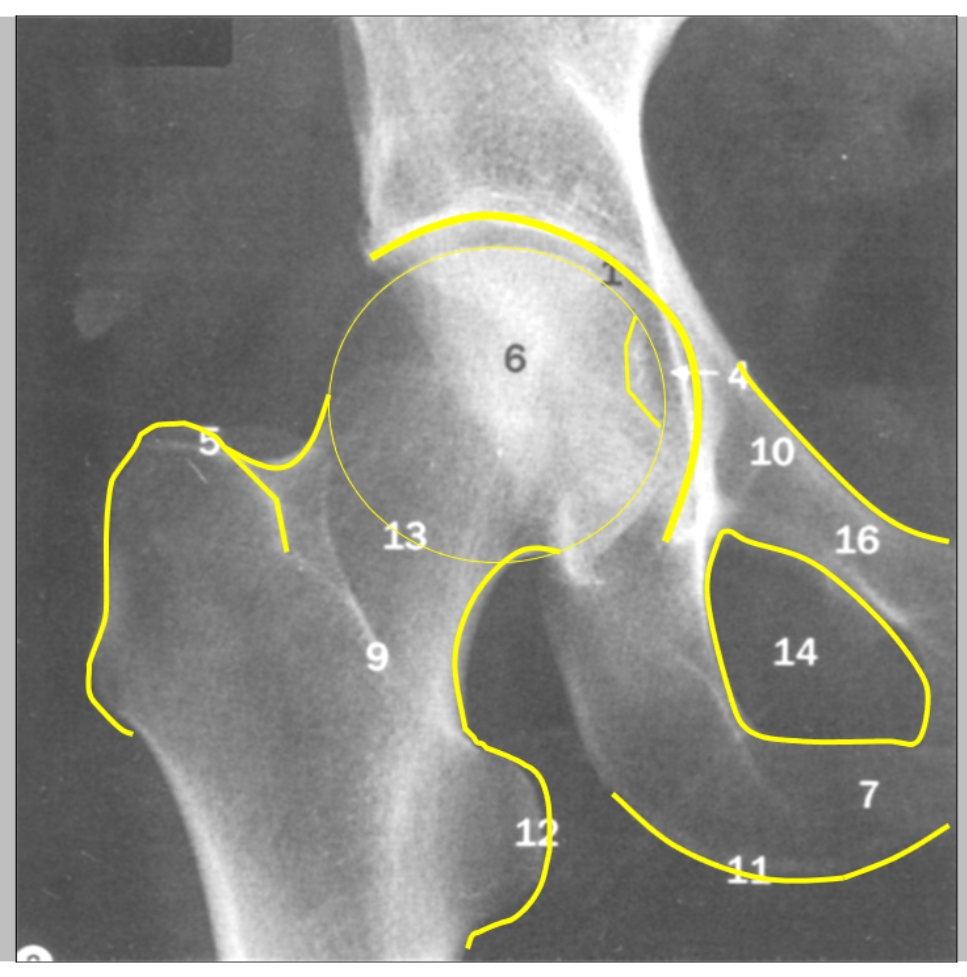

acetabulum

fovea capitis femoris

ligamentum capitis femoris ligt hierop vast

trochanter major

apofyse

caput femoris

ramus inferior

ramus superior

tuber ischiadicum

trochanter minor

pees van de m. iliopsoas ligt hierop

collum femoris

foramen obturatorium

→ rechter heup